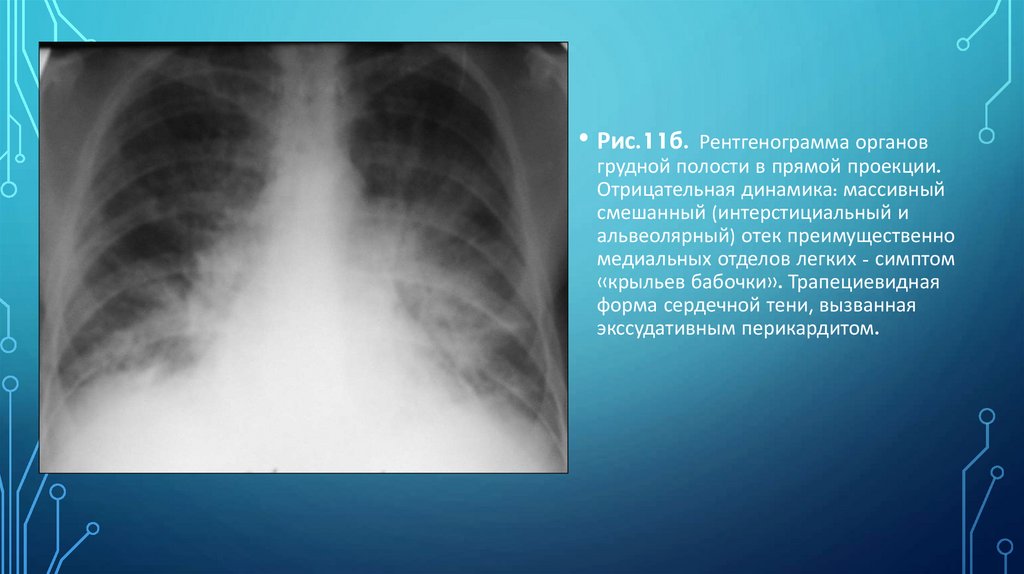

• Рис.11б. Рентгенограмма органов

грудной полости в прямой проекции.

Отрицательная динамика: массивный

смешанный (интерстициальный и

альвеолярный) отек преимущественно

медиальных отделов легких - симптом

«крыльев бабочки». Трапециевидная

форма сердечной тени, вызванная

экссудативным перикардитом.

109. Рис. 18. Пациент М. 65л. Диагноз: Инфаркт миокарда. Перикардит. Кардиогенный отек. Синдром диффузных изменений легочного

РИС. 18. ПАЦИЕНТ М. 65Л. ДИАГНОЗ: ИНФАРКТ МИОКАРДА.

ПЕРИКАРДИТ. КАРДИОГЕННЫЙ ОТЕК. СИНДРОМ ДИФФУЗНЫХ

ИЗМЕНЕНИЙ ЛЕГОЧНОГО РИСУНКА И СИНДРОМ ДИССЕМИНАЦИИ.

СИНДРОМ ПАТОЛОГИИ КОРНЕЙ.